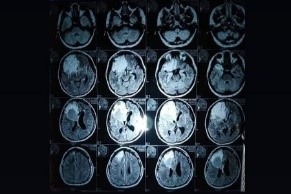

Lamentablemente hace meses atrás fui diagnosticada con dos tumores cerebrales en el lóbulo frontal izquierdo, me entere a través de una resonancia magnética, por los siguientes síntomas: pérdida de visión, alucinaciones, vómitos excesivos, perdida de coordinación, demencia, afectando el habla, la movilidad del lado izquierdo de mi cuerpo, insomnios constantes por los fuertes dolores de cabeza debido a la inflamación, llegue al hospital público de mi país para un chequeo y me dan la mala noticia que tenía que ser operada de emergencia, por exceso de líquido céfalo raquídeo en el cerebro por Hidrocefalia a causa del tumor, lo cual me colocaron una válvula ventriculoperitoneal que va conectada del cerebro a mi vejiga para extraer el líquido que ahora debo tenerla permanentemente.  Adjunto la papelería de diagnósticos que validan mi enfermedad y lo que necesito.

A raíz de esa operación quede internada 4 meses, esperando la segunda cirugía y extraer los tumores para posteriormente ingresar a intensivo al tratarse de algo tan delicado, misma que fue realizada el 9 de enero del presente año. Tuve una crisis (recaída) días después de la cirugía, donde prácticamente quede en coma por 3 días, luego, convulsiones seguidas, vómitos excesivos, desmayos y quedar inconsciente otros días. En ese momento los médicos le dan la noticia a mi familia que no pudieron extraer todo el tumor por ser maligno un (Glioblastoma Multiforme grado 4 (cancerígeno).

Actualmente me hicieron tres resonancias el Neurocirujano y Oncóloga me indicaron que necesito una tercera cirugía y tratar de extraer todo el tumor misma que estaré sometiéndome en cuanto me den la fecha dado que por la pandemia está siendo más complicado todo, también tengo un desgaste de cartílagos en las vertebras debido al alto consumo de esteroides, cuesta mucho movilizarme por lo que a veces uso silla de ruedas ya que algunos medicamentos han tenido efectos secundarios en subir de peso, perjudicando mis riñones, hígado, hormonas, dolor de huesos fuertes, necesito terapias en pies y piernas. Mi padre falleció hace algunos años y tengo a mi madre con quebrantos de salud, la pandemia nos ha afectado tanto aún más en la situación en la que me encuentro.  Soy una mujer de fe donde se que saldré de esta prueba.